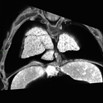

| Mutant 2459-006-1 (E16.5) exhibits malalignment of the great arteries, shown to be double outlet right ventricle (DORV) by EFIC imaging | b2b2459Clo/b2b2459Clo | C57BL/6J-b2b2459Clo |

| EFIC Summary | b2b2459Clo/b2b2459Clo | C57BL/6J-b2b2459Clo |

| Serial 2D EFIC image stack in the coronal plane of 2459-006-1 (E16.5) shows DORV, AVSD, RV non-compaction, LV hypertrophy, and cushion-like valves

Click thumbnail to play movie. | b2b2459Clo/b2b2459Clo | C57BL/6J-b2b2459Clo |